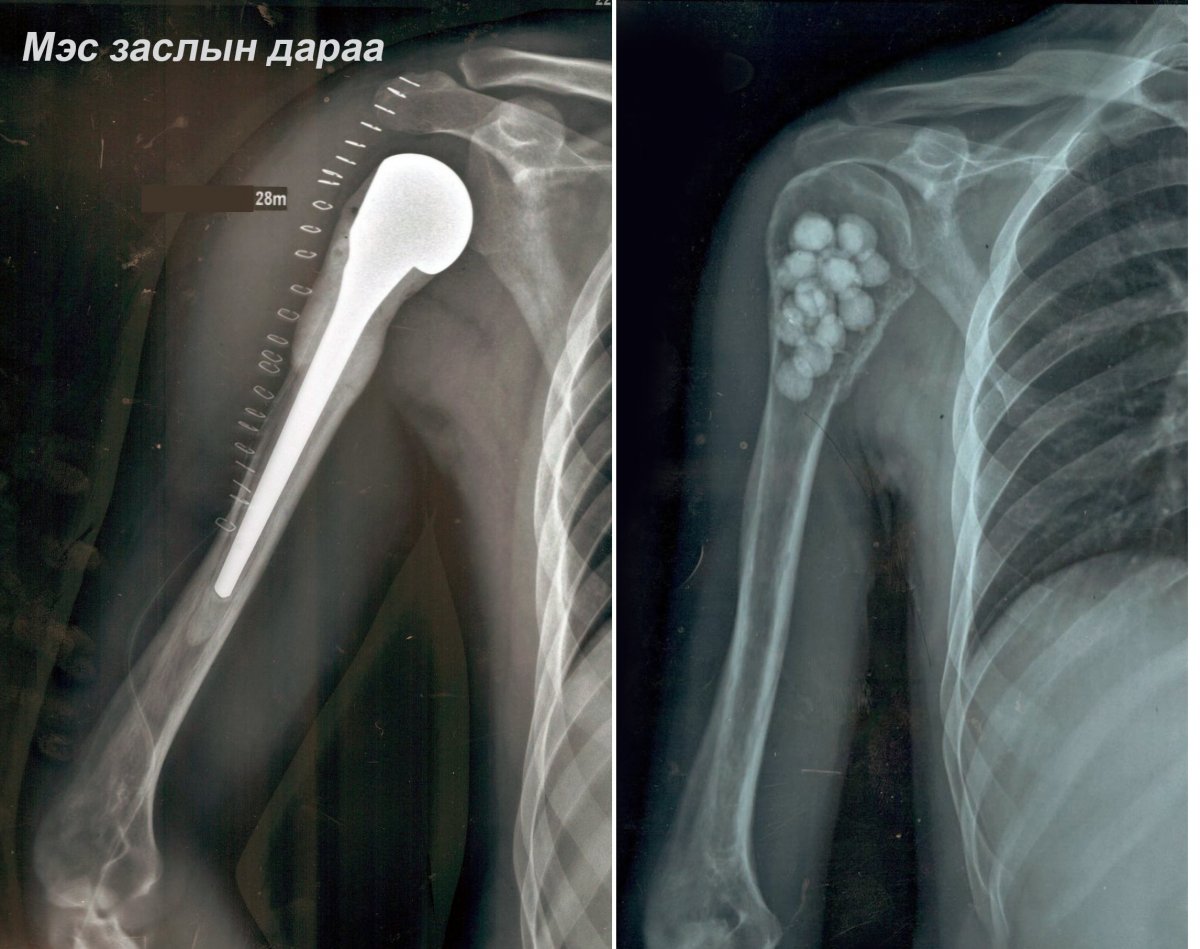

САЙН МЭДЭЭ: ГССҮТ, ХСҮТ-ийн эмч нар хамтран эрхтэн хадгалах МЭС ЗАСЛЫГ амжилттай хийлээ

ГССҮТ, ХСҮТ-ийн ерөнхий мэс заслын эмч нар хамтран эрхтэн хадгалах мэс заслыг 2020 оны 21-ний амжилттай хийлээ. Тодруулбал, Эмчлүүлэгч 28 настай, эрэгтэйн баруун талын атгаал ясны дээд хэсгийн хорт хавдрыг авч баруун талын атгаал ясыг тайран мөрний үеийг сольсон эрхтэн хадгалах мэс засал болжээ.